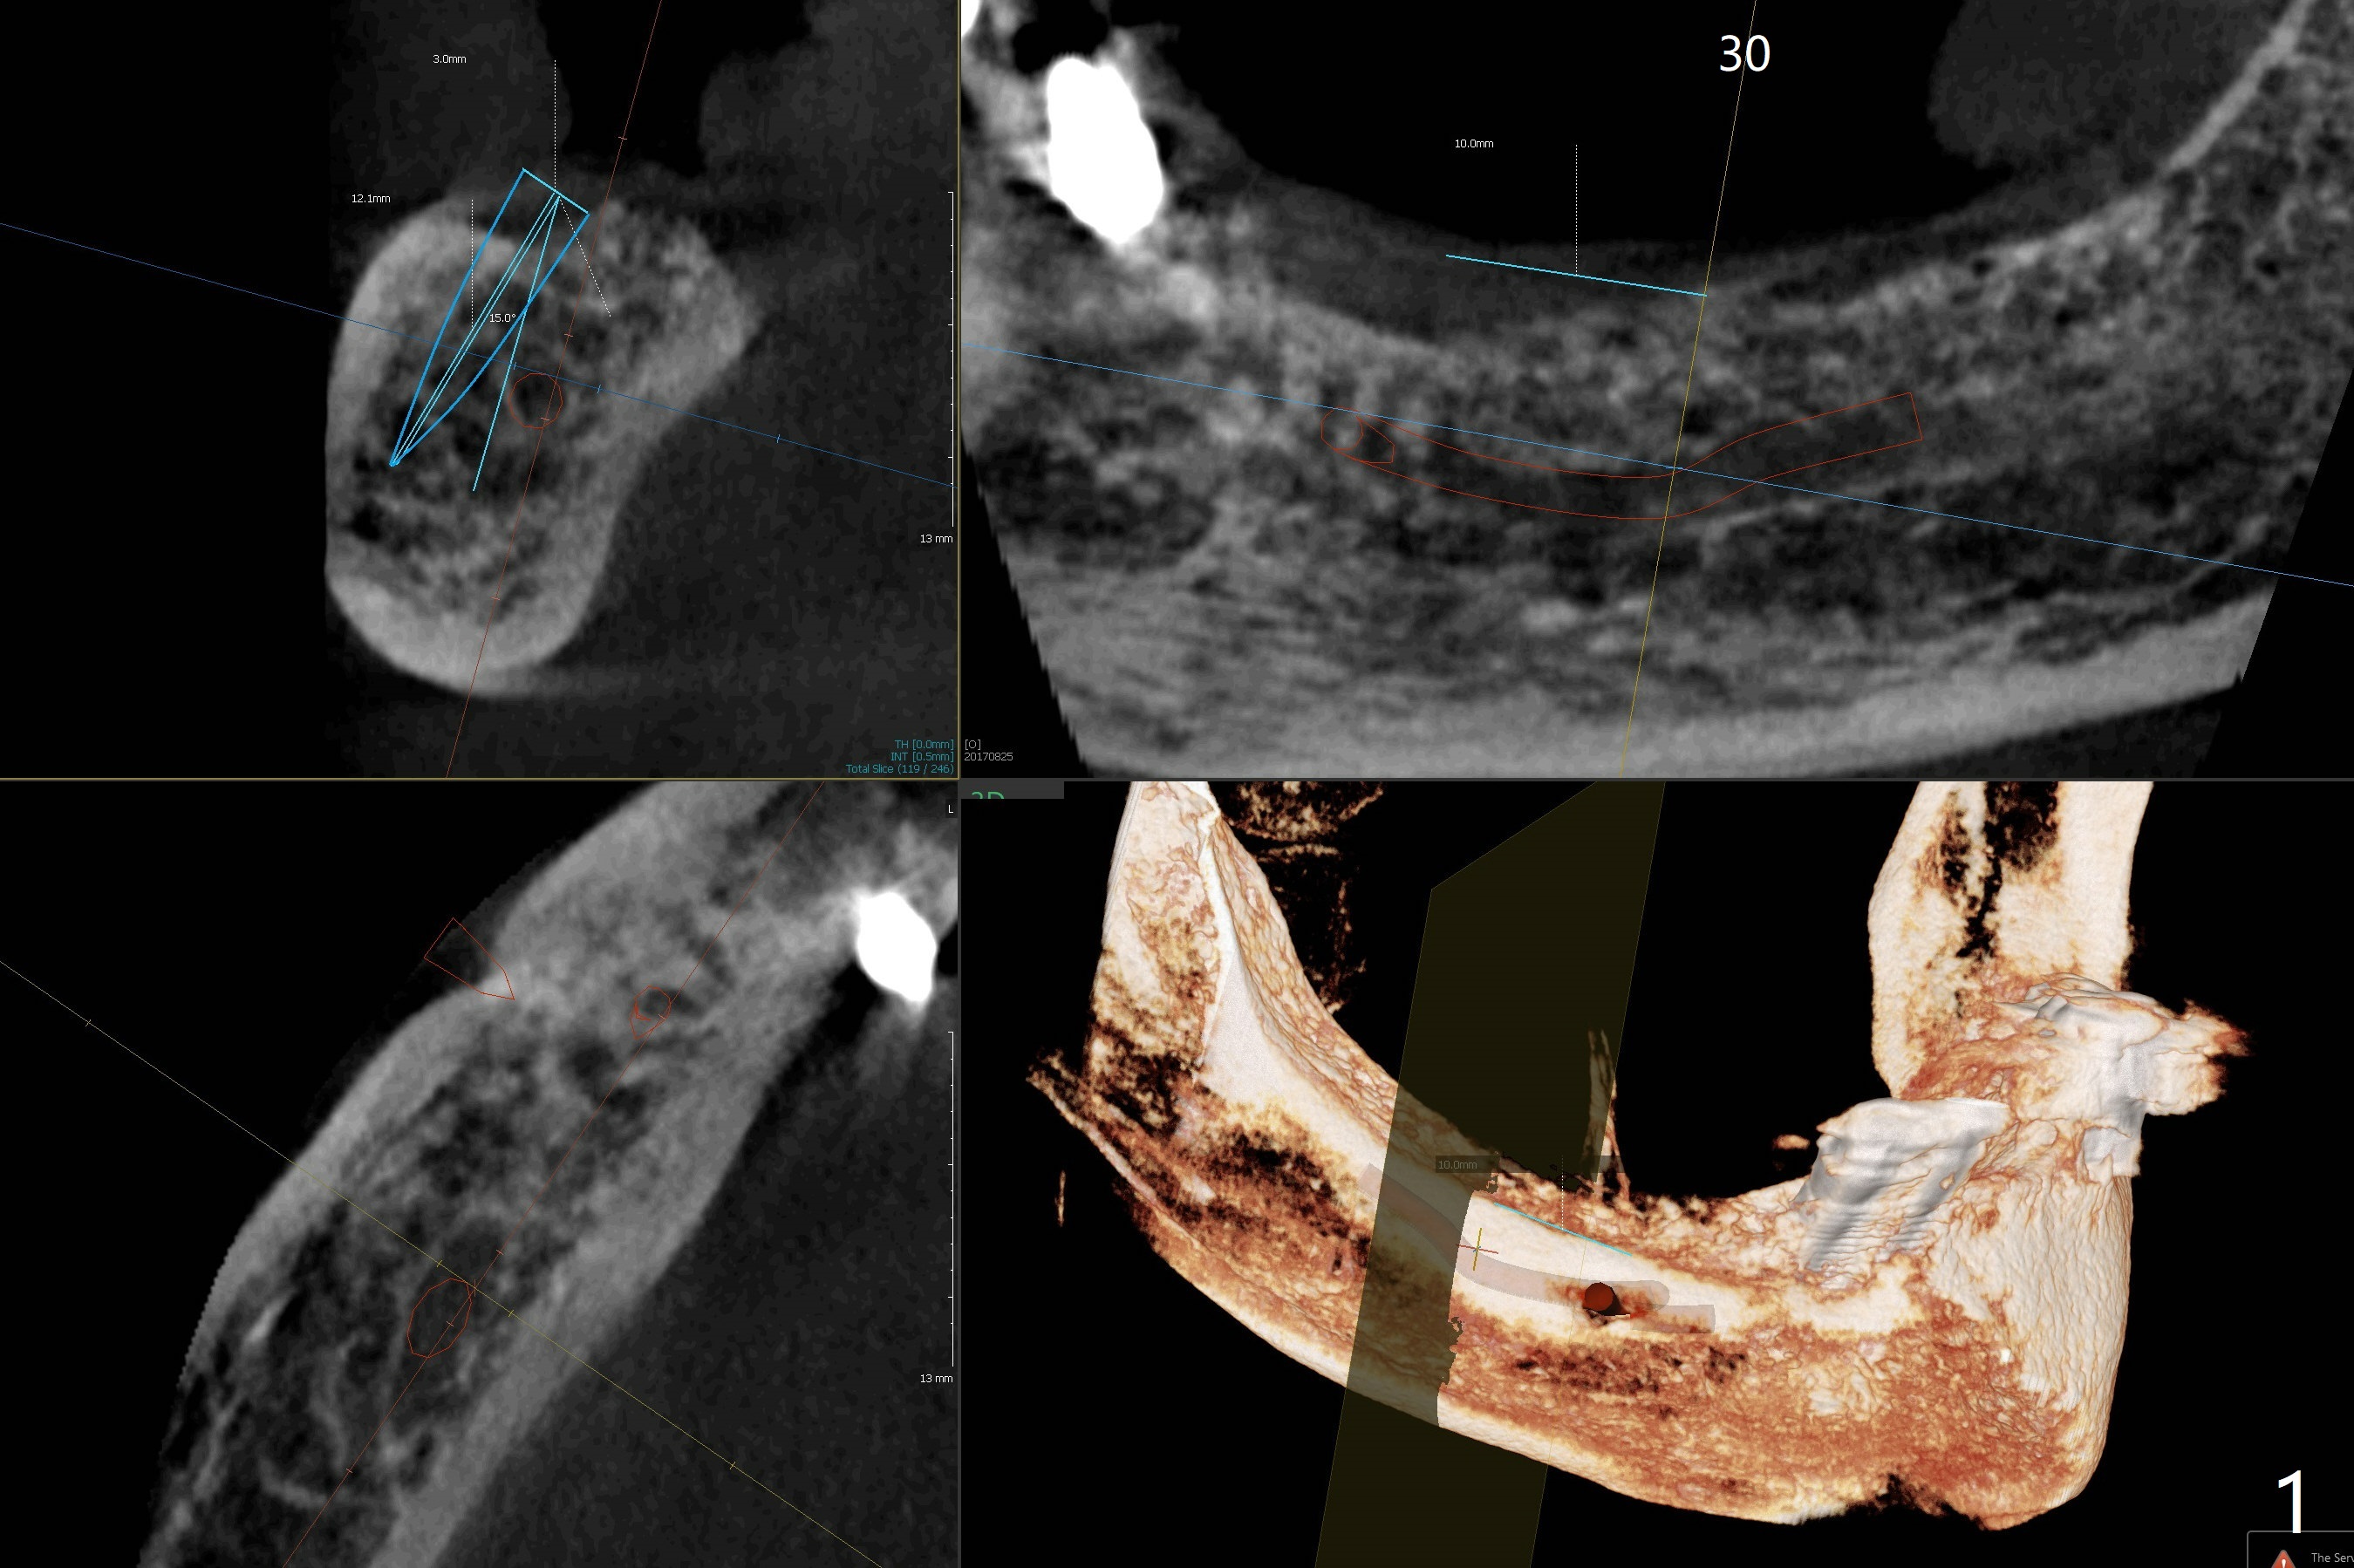

Following placement of a 3 mm 1-piece implant at #26 and two 3.8 mm 2-piece implants with ball abutments at #20 and 21 for a lower edentulous patient, another implant with ball abutment will be placed posterior (approximately at #30, Fig.1,2 (for better spread)) or anterior (approximately at #28, Fig.3,4). The implant will be placed buccal (Fig.2) or lingual (Fig.4) to the Inferior Alveolar Canal or Incisive Canal (safer). Or an implant can be placed at #27, in which there have been 2 implant failures. The last implant was removed 3 months 20 days earlier. Make an incision, study whether the site of #27 has healed with solid bone. If an implant has to be placed at #28, dissect the Mental Nerve first. When stability is low, bury the implant.